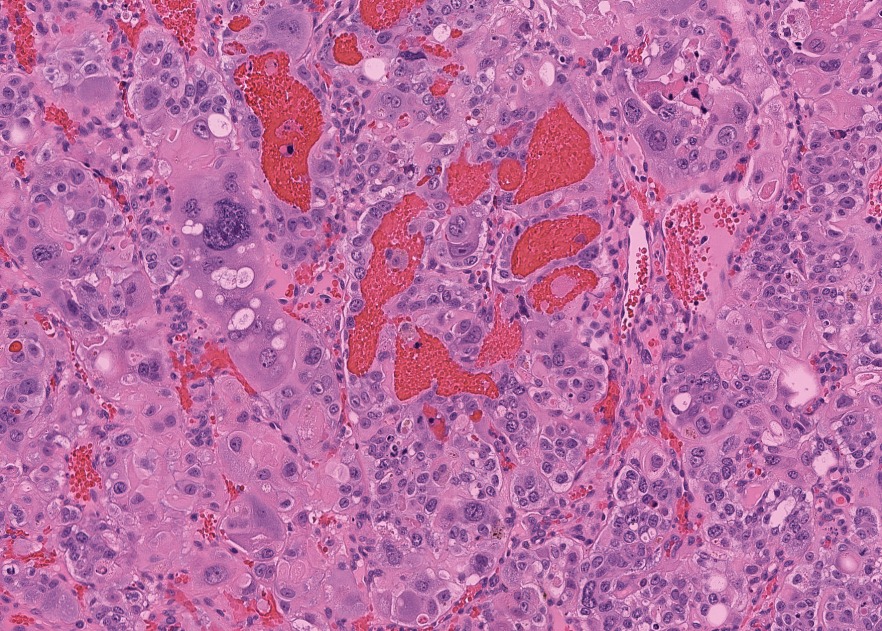

- Wide spectrum of trophoblastic differentiation, ranging from scattered isolated cells with trophoblastic differentiation to pure choriocarcinoma

- Often admixed with conventional urothelial carcinoma or other variants / subtypes

- When present as scattered isolated cells, they can be in the form of cytotrophoblasts (usually indistinguishable from high grade urothelial carcinoma or syncytiotrophoblast (recognizable by their multinucleated giant cells)

- Resembles choriocarcinoma in other organs

Microscopic (histologic) images